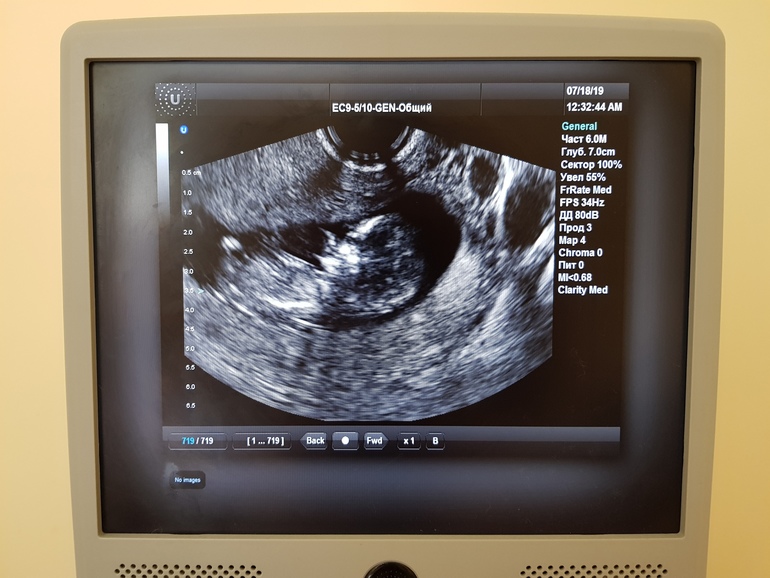

Пол малышаПривет девочки 🤗 Знаю, что глупо... Но иногда Вы отвечаете на такие посты. Как думаете, по снимку можно предположить пол?)))))) Я в этом вообще ничего не понимаю, у врача даже не спросила, у нас в ЖК такая текучка - всё быстро быстро.

Качество фото вообще не очень, чтобы предположить. У нас на этом сроке уже пипка торчком была))) но это скорее исключение, что так рано все уже видно четко

Больше похоже на девочку, т.к. попка закинута слегка и если развернуть чуть бугорок будет параллельно позвоночнику. Но если честно, не самый удачный кадр

Наверно девочка, малыш попой вверх лежит, либо снимок такой, если экран немного перевернуть, половой бугорок четко по позвоночнику будет, не вверх. А вообще, ждите 2 скрининга, столько историй с этими определениями, что уже ничему не веришь))

Не параллельно, повыше, похоже на мальчика.

Но на этом сроке пол определяется с той же вероятностью, как просто угадать, - 50%🤷🏼♀️.